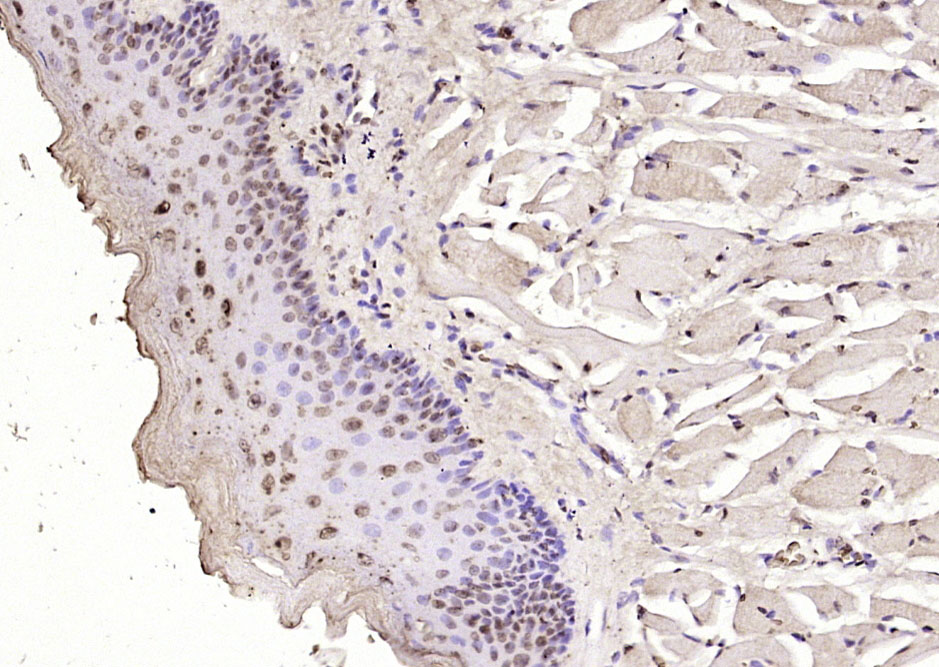

Paraformaldehyde-fixed, paraffin embedded (mouse liver tissue); Antigen retrieval by boiling in sodium citrate buffer (pH6.0) for 15min; Block endogenous peroxidase by 3% hydrogen peroxide for 20 minutes; Blocking buffer (normal goat serum) at 37°C for 30min; Antibody incubation with (FGGY) Polyclonal Antibody, Unconjugated (bs-11689R) at 1:400 overnight at 4°C, followed by operating according to SP Kit(Rabbit) (sp-0023) instructionsand DAB staining.

Paraformaldehyde-fixed, paraffin embedded (rat kidney tissue); Antigen retrieval by boiling in sodium citrate buffer (pH6.0) for 15min; Block endogenous peroxidase by 3% hydrogen peroxide for 20 minutes; Blocking buffer (normal goat serum) at 37°C for 30min; Antibody incubation with (FGGY) Polyclonal Antibody, Unconjugated (bs-11689R) at 1:400 overnight at 4°C, followed by operating according to SP Kit(Rabbit) (sp-0023) instructionsand DAB staining.

Paraformaldehyde-fixed, paraffin embedded (rat tongue); Antigen retrieval by boiling in sodium citrate buffer (pH6.0) for 15min; Block endogenous peroxidase by 3% hydrogen peroxide for 20 minutes; Blocking buffer (normal goat serum) at 37°C for 30min; Antibody incubation with (FGGY) Polyclonal Antibody, Unconjugated (bs-11689R) at 1:400 overnight at 4°C, followed by operating according to SP Kit(Rabbit) (sp-0023) instructionsand DAB staining.